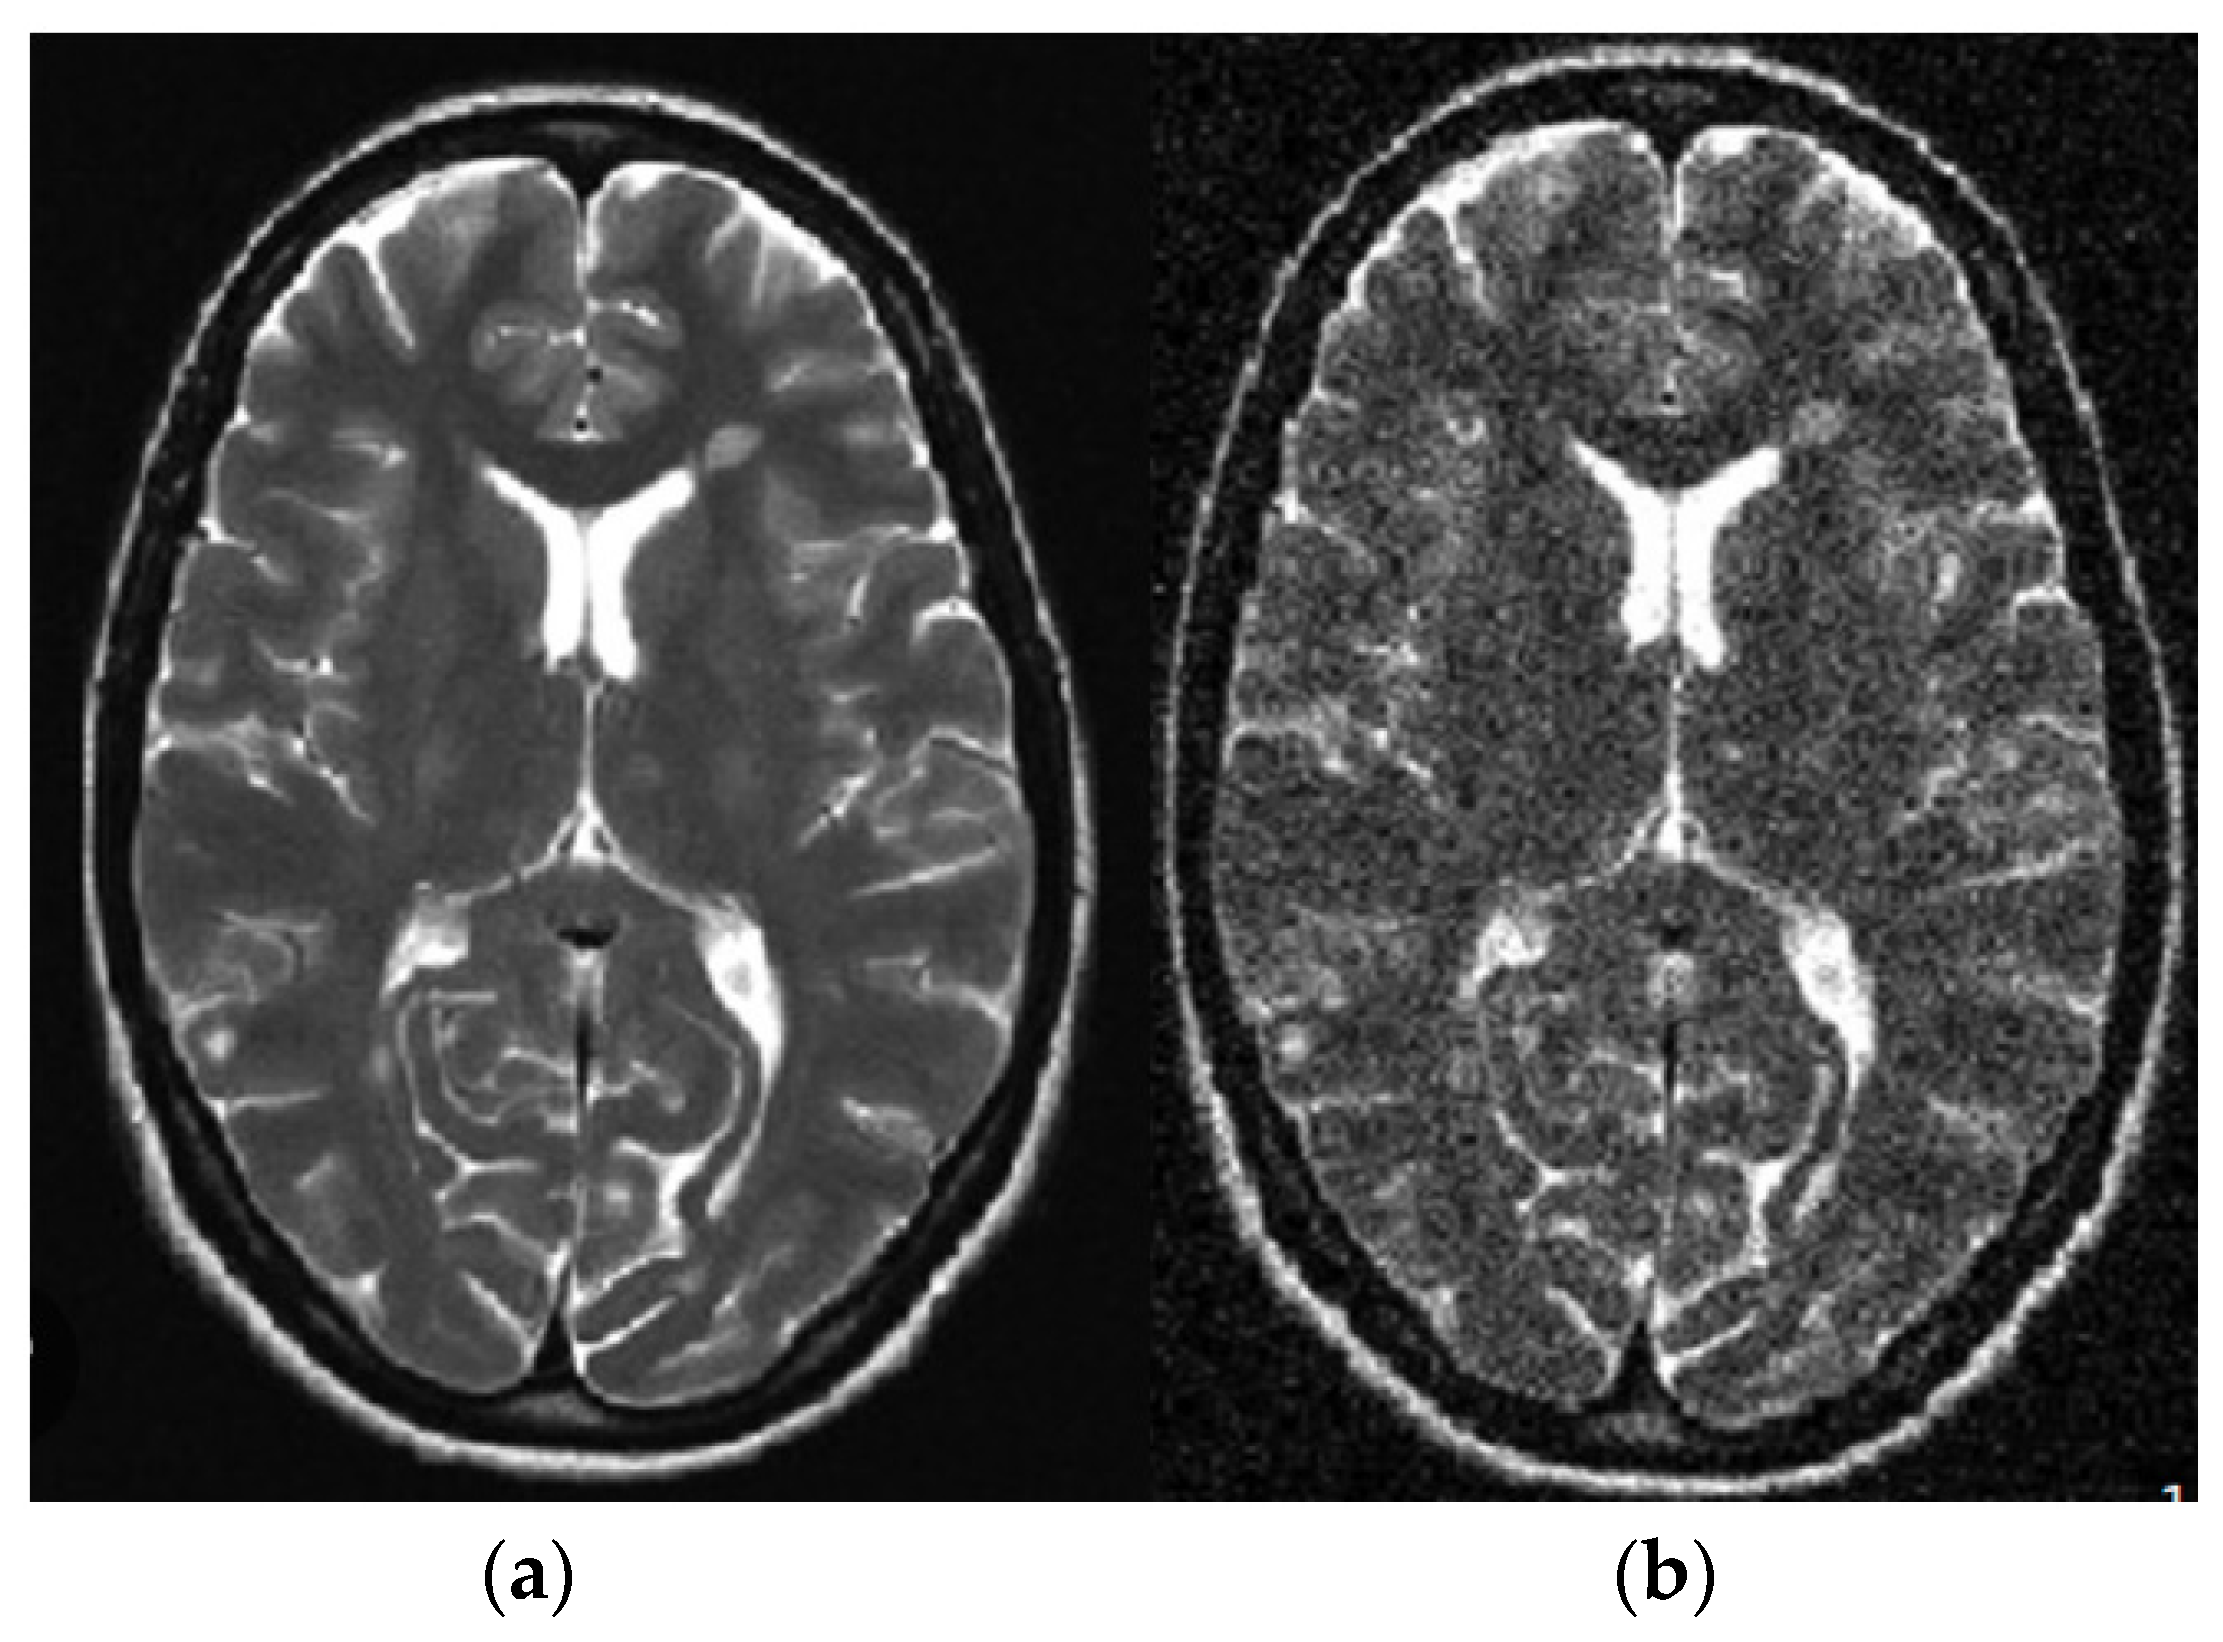

3.1. Stage 1: Pre-Processing—Linear Adaptive Filter